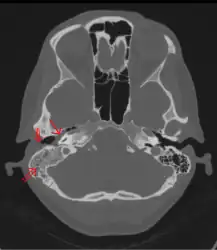

The diagnosis of mastoiditis is clinical—based on the medical history and physical examination. Imaging studies provide additional information; The standard method of diagnosis is via MRI scan although a CT scan is a common alternative as it gives a clearer and more useful image to see how close the damage may have gotten to the brain and facial nerves. Planar (2-D) X-rays are not as useful. If there is drainage, it is often sent for culture, although this will often be negative if the patient has begun taking antibiotics. Exploratory surgery is often used as a last resort method of diagnosis to see the mastoid and surrounding areas.[7][8]